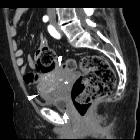

Giant

fibroepithelial polyp of the uterine cervix. After intravenous contrast the dorsal hyperattenuating portion (*) did not enhance. Arterial-phase early enhancement was noted in the anterior solid portion of the enlarged cervix (arrowheads), without contrast extravasation suggesting active bleeding.